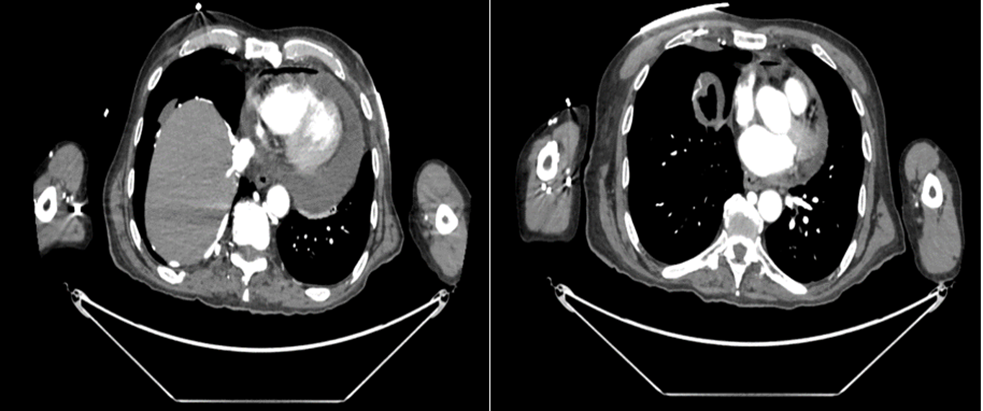

A 67-year-old man with hypothyroidism and end-stage metastatic lung carcinoma with poor prognosis presented with rapidly worsening dyspnea. The initial electrocardiogram (ECG) showed sinus rhythm with ST-segment elevation in leads II, III, aVF, I, V5, and V6, and reciprocal ST depression in V1 and aVR. Careful review of the baseline tracing demonstrated a Spodick sign. (Figure 1) Transthoracic echocardiography (TTE) revealed a large circumferential pericardial effusion up to 3.5 cm. Emergency computed tomography angiography (CTA) of the thoracic and abdominal aorta was performed to exclude acute aortic dissection at the level of the right coronary sinus of Valsalva. No evidence of dissection was found. CTA demonstrated a large pericardial effusion with associated pneumopericardium, a right-sided pneumothorax with partial collapse of the upper lobe, pneumomediastinum, and pneumoperitoneum. The largest lesion was located in the right upper lung field and was considered a probable site of air entry into the pericardial sac through communication with the mediastinum. In addition, pathological mediastinal and hilar lymphadenopathy, as well as hepatic and osseous metastases, were noted. (Figure 2)

Figure 2: CTA showing large pericardial effusion and pneumopericardium.